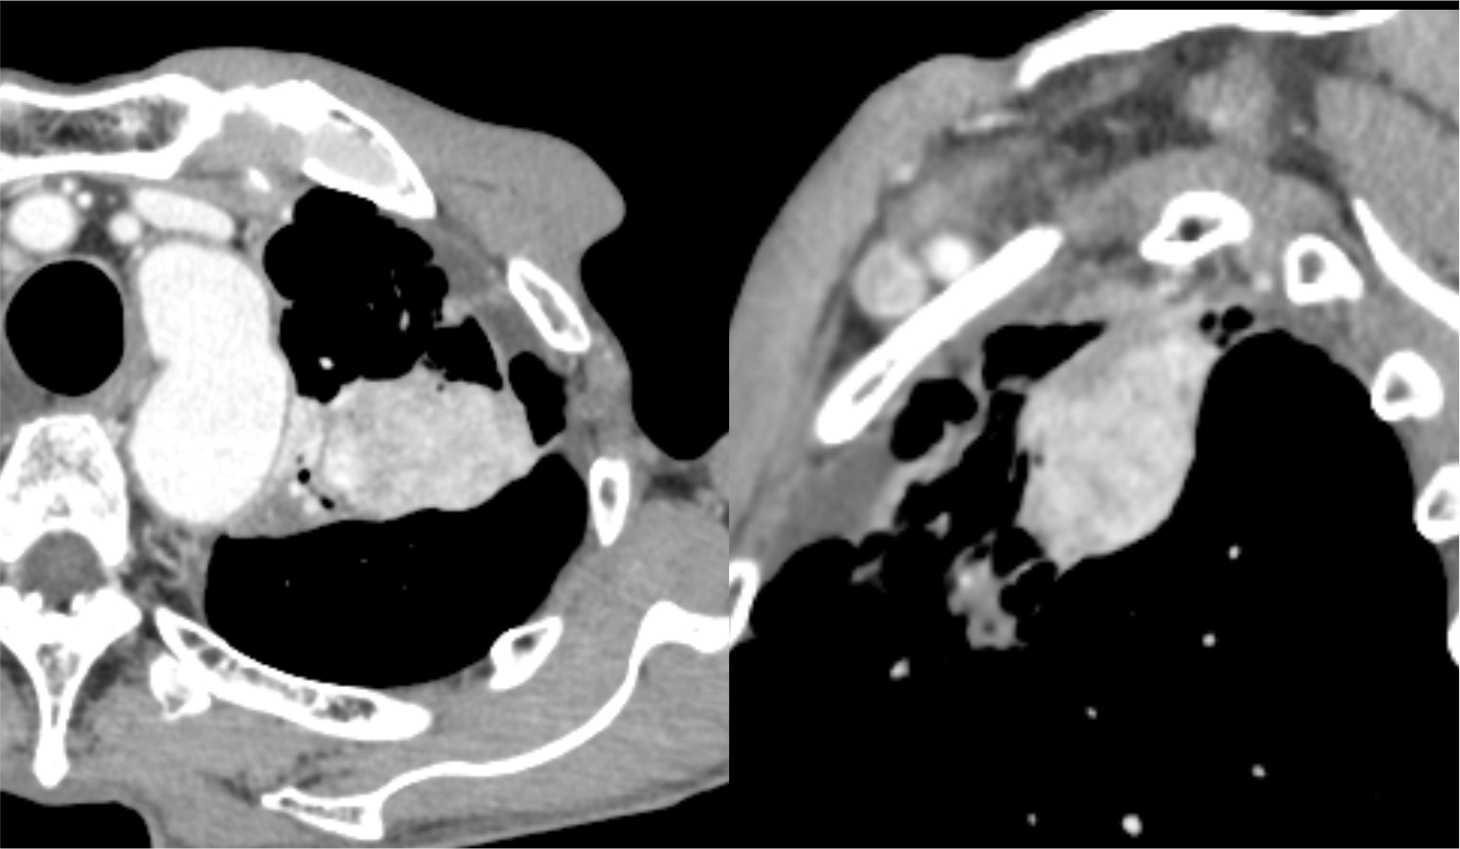

図5.造影CT後期相(Virtual Monoenergetic Image 100keV表示)

100keV表示では、造影効果は減弱しているが、ノイズは軽減している。